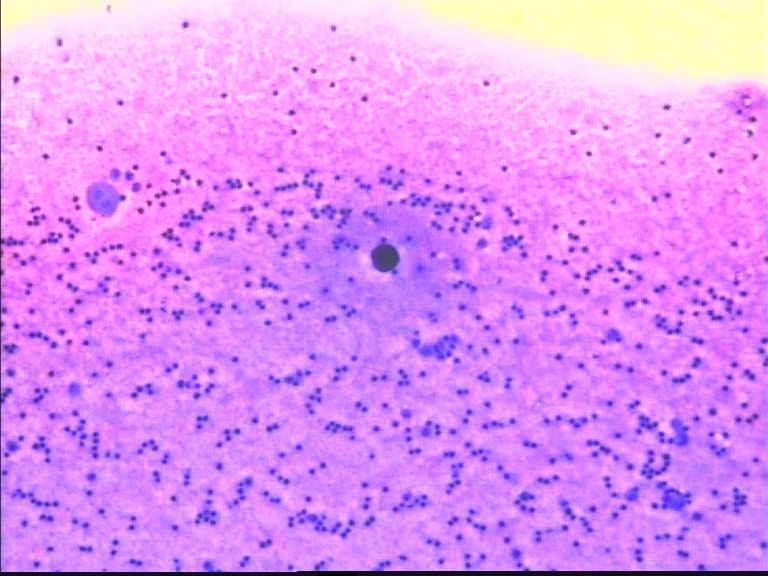

67岁,胸水

看不清细胞结构,模糊中感觉淋巴和间皮细胞

我就是想知道这个深染的是什么?

图片欠清   深染的是什么?

染色过深,固定不及时。那个核浆比高的细胞是异物还是细胞啊?不好判断。

模糊不清,性质难定。建议,改善制片。